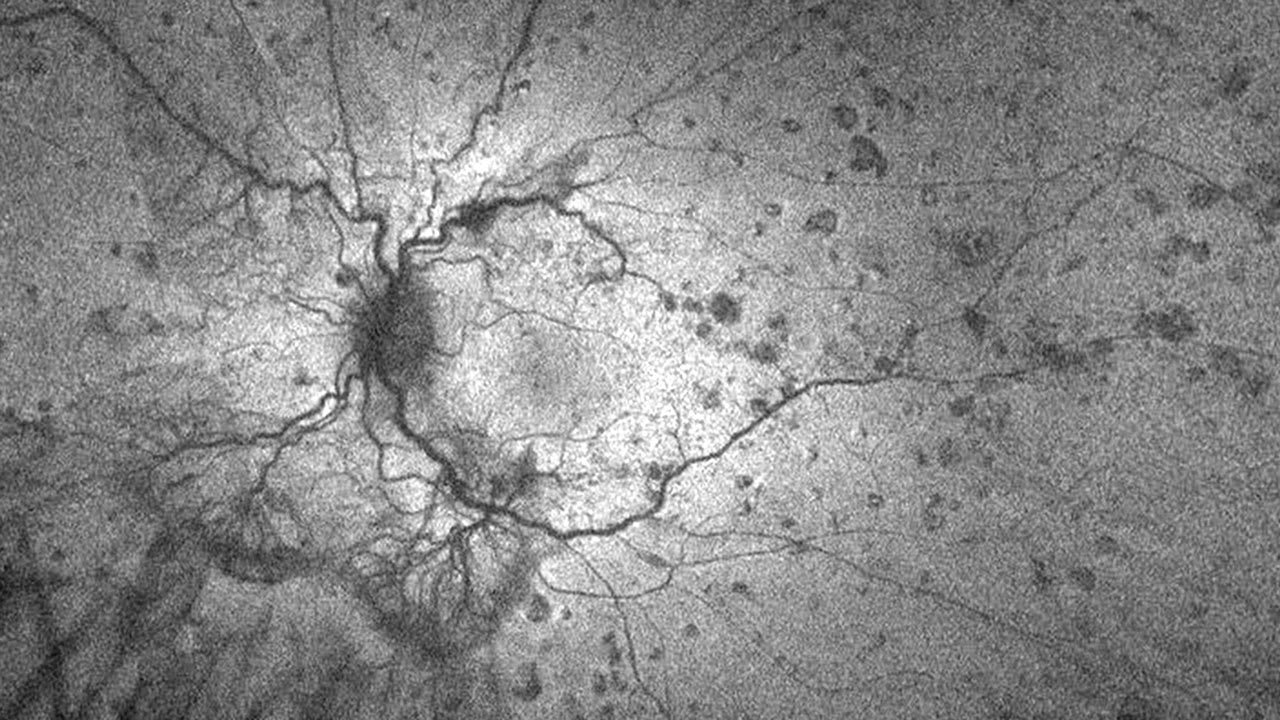

- Compromised retinal circulation. Glaucoma exacerbates retinal ischemia by further reducing blood perfusion in a retina already compromised by diabetes. This may accelerate the onset and progression of DR, increasing the likelihood of proliferative DR.

- Structural damage. Progressive optic nerve damage in glaucoma may decrease retinal nerve fiber layer (RNFL) thickness, which is shown to correlate with DR severity.9 This suggests a synergistic effect in which both diseases amplify neuronal loss.

- Reduced tolerance to IOP fluctuations. In diabetics who have glaucoma, retinal vasculature may be less capable of adapting to IOP fluctuations. This can result in greater susceptibility to retinal hypoxia, neovascularization, and, eventually, vision-threatening complications, such as vitreous hemorrhage and tractional retinal detachment.